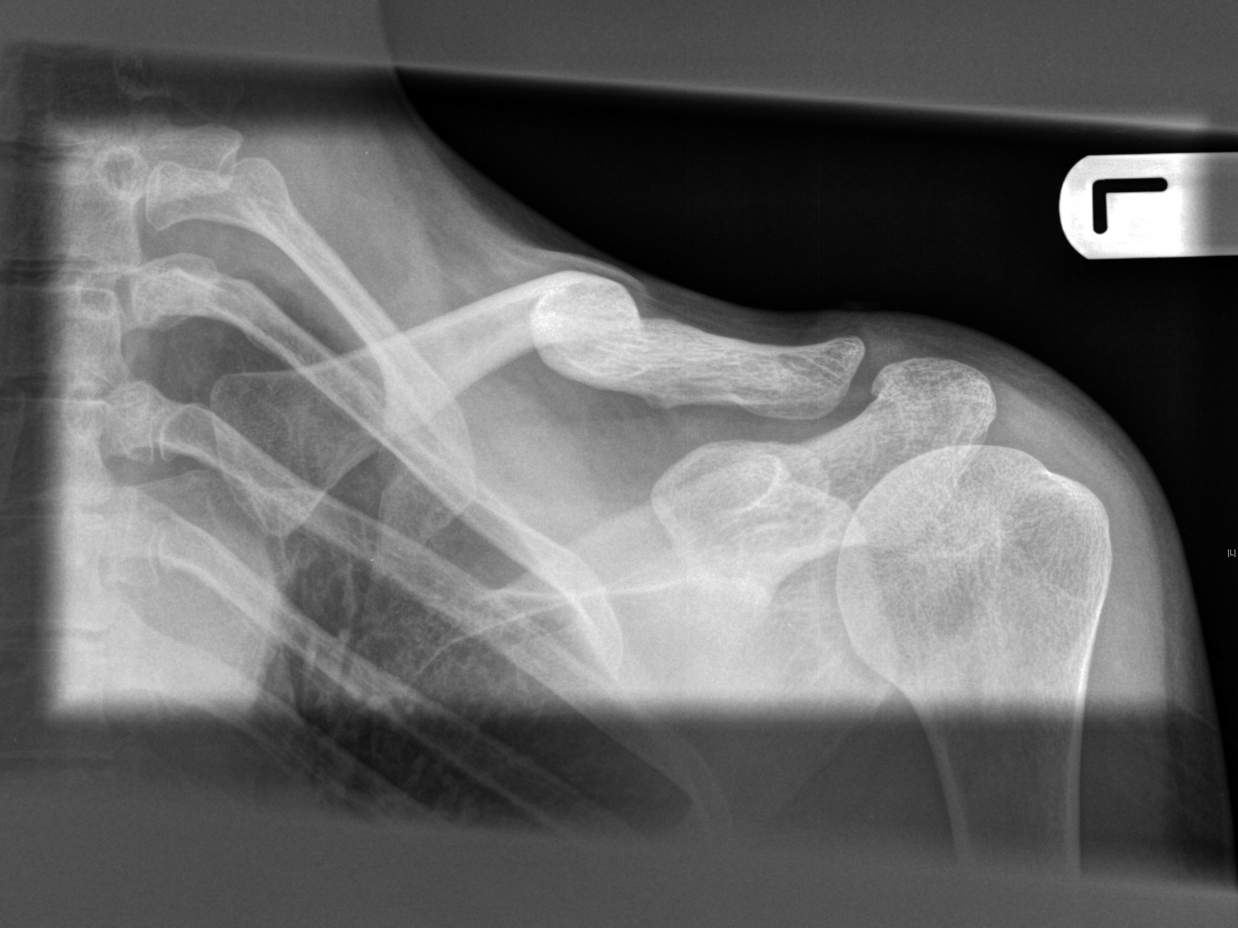

After breaking my collarbone three times I decided that I would ride more safely and not get airborne. On my first ride out we stopped at a little learning drop jump for new people to practice on and I agreed to lead them into it. It was only a two feet drop but it was enough to instil the sensation of freefall. I feel good; in tune with my body and focused within the present. Around the corner is a ten feet gap jump, shortly followed by a kicker that sends me soaring into the air, I feel electric. In ‘Broken Arm’ Henri Michaux also observes this phenomena, ‘Soon forgetful – forgetting now in the other direction (one consciousness excludes the other) – I was beginning to use my arm again in a matter-of-fact way...’ (1994: 249).

I find the attraction to push to the limits of breaking, both in my artwork and in mountain biking, increases the more I do them. I enjoy the element of risk, and this enjoyment encourages further risk. Deborah Lupton (2013: 207) observes that adrenaline allows the body’s senses and emotion to take over from the rational mind. Risk taking in making could be carrying too many unfired bone china twigs or creating moulds and pieces that stretch technical limitations. In biking this involves larger and more dangerous gap jumps and steeper technical descent closer to cliff edges. However when I am injured and look at photographs of me airborne on my bike I feel it was stupid to take such risks. Lupton (2013: 203) notes, ‘the emphasis in contemporary societies on the avoidance of risk is strongly associated with the ideal of the ‘civilized’ body, an increasing desire to take control of one’s life, to rationalise and regulate the self and body, to avoid the vicissitudes of fate….To take unnecessary risks is commonly seen as foolhardy, careless, irresponsible and even deviant…’ Oliver Sacks notes after his injury he, ‘would see all life, all being, as the most precious gifts, infinitely vulnerable and precarious, to be infinitely prized and cherished’ (1990: 187). For me this view vanishes again as soon as I return to the risk-taking activities. When I am injured in addition to seeing risk taking as foolhardy I also long for excitement to break from the restricted movement of my injured body. This indicates the complexity of the balance between ontological security and risk taking.